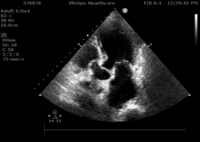

此患者为86岁男性,因“突发胸痛、胸闷28小时”入院,诊断为急性心肌梗死,合并快室率房颤、肺部感染、慢性肾功能衰竭,入院后在积极药物及IABP辅助下心衰仍难以控制,查体出现心尖部收缩期杂音,心脏彩超提示“二尖瓣前瓣脱垂(A2区为主)并重度关闭不全,瓣尖见条索状回声随心动周期摆动”(视频1、视频2 、视频3)。术前,武汉亚总和亚心医院结构性心脏病多学科团队对该患者病情进行了反复讨论,认为该高龄患者急性心肌梗死后出现机械并发症,且合并多器官功能不全,心功能不全难以纠正,死亡率极高,外科开胸手术风险极高(STS评分>30),决定选择微创经导管二尖瓣夹合术。

3月30日患者先在全麻下进行TEE(经食道超声心动图)再次评估瓣膜情况(视频4、视频5、视频6 ),确定为二尖瓣前组乳头肌断裂致二尖瓣前瓣脱垂并重度返流,其脱垂部位、瓣叶结构、瓣口面积等适合进行二尖瓣夹合术。术中IABP辅助,ECMO湿备,穿刺右侧股静脉,在TEE指导下顺利穿刺房间隔,随后送入二尖瓣夹合系统,在超声指导下于二尖瓣A2/P2区植入一枚Mitraclip XTR夹合器(视频7),术后TEE评估返流程度从5+降至1+(视频8 ),夹合结果满意,二尖瓣呈双孔启闭(视频9 ),术后二尖瓣平均跨瓣压差1mmHg(图1),收缩期肺静脉返流消失(图2 ),手术总耗时80min。香港亚洲医疗中心林逸贤教授通过视频连线进行手术全程技术支持。